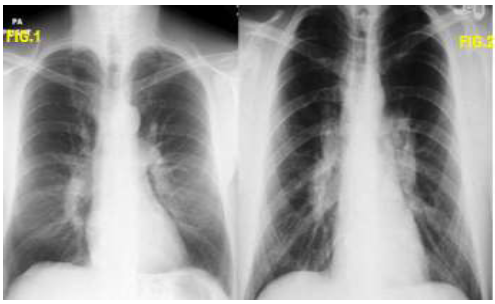

Analise as duas imagens abaixo e assinale a alternativa correta:

Analise as duas imagens abaixo e assinale a alternativa correta: